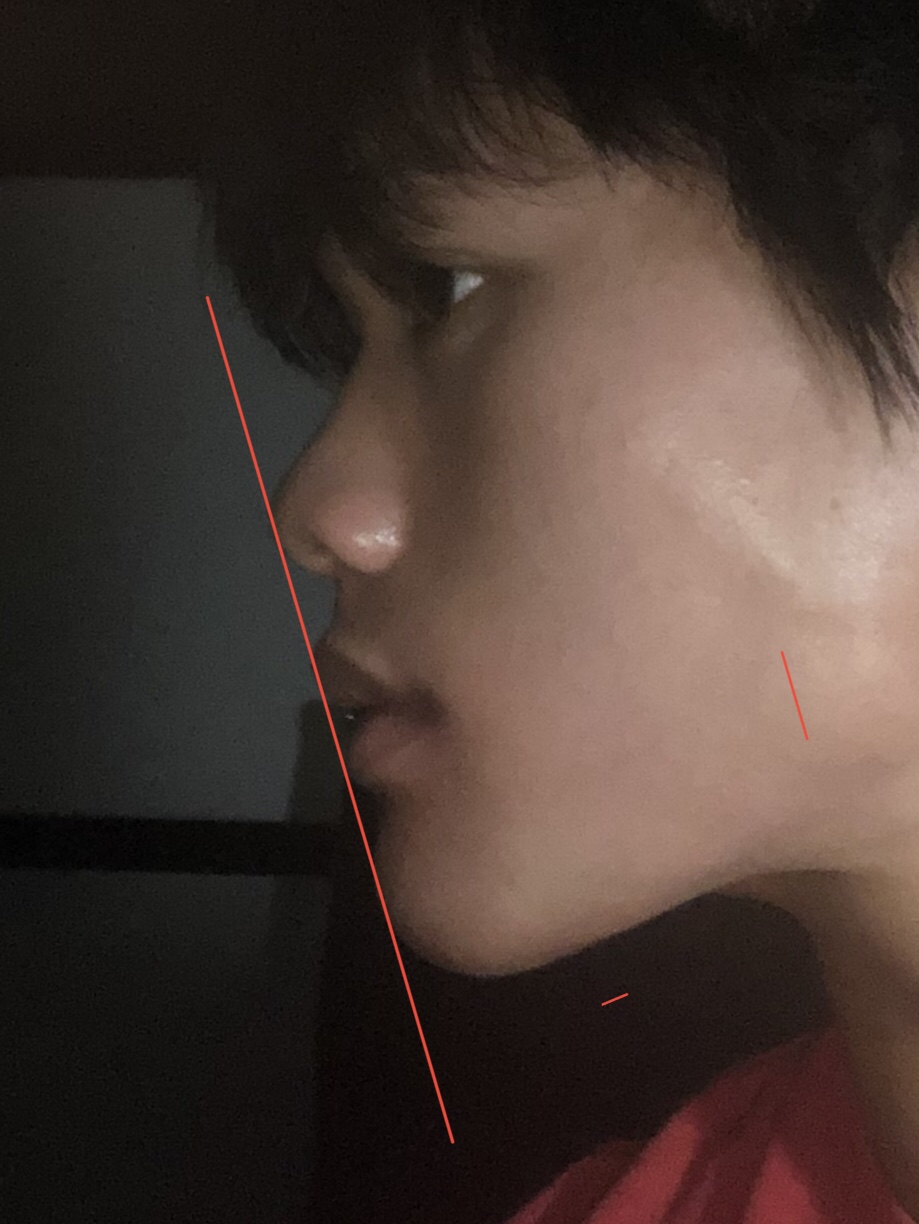

As seen above, my Ricketts-E Plane is shit.

As seen above, my Ricketts-E Plane is shit.